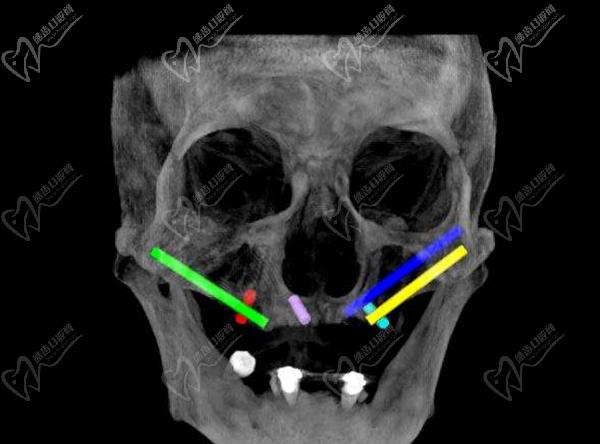

第三步:种植牙

接下来,医生会在必要的位置上植入种植体。这些种植体充当人工牙根,用于支撑和固定新的牙齿。采用数字化智能种植技术,上下牙颌各仅需要4-6颗植体就能恢复半口牙14颗牙齿。